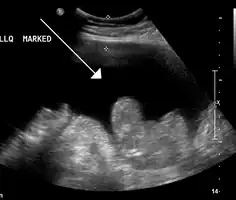

Ascites in a person with abdominal cancer as seen on ultrasound

Ultrasound investigation is often performed prior to attempts to remove fluid from the abdomen. This may reveal the size and shape of the abdominal organs, and Doppler studies may show the direction of flow in the portal vein, as well as detecting Budd-Chiari syndrome (thrombosis of the hepatic vein) and portal vein thrombosis. Additionally, the sonographer can make an estimation of the amount of ascitic fluid, and difficult-to-drain ascites may be drained under ultrasound guidance. An abdominal CT scan is a more accurate alternate to reveal abdominal organ structure and morphology.